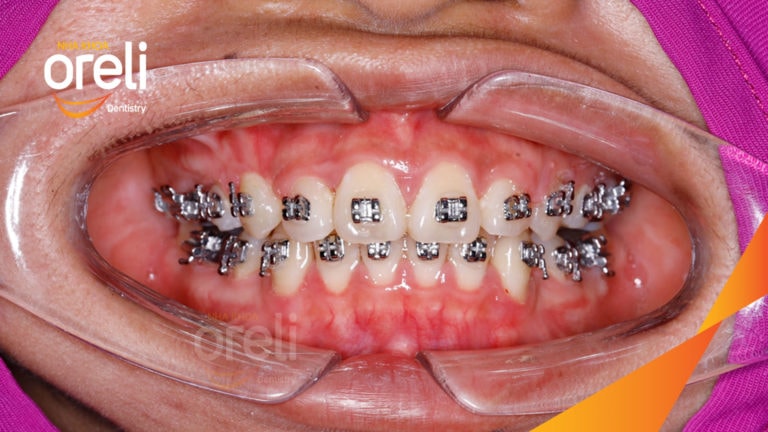

Ca niềng răng sai khớp cắn hạng 3 móm nặng có nhổ răng số 7 – Kết quả thực tế Niềng răngChỉnh lệch cằmMóm Xem thêm